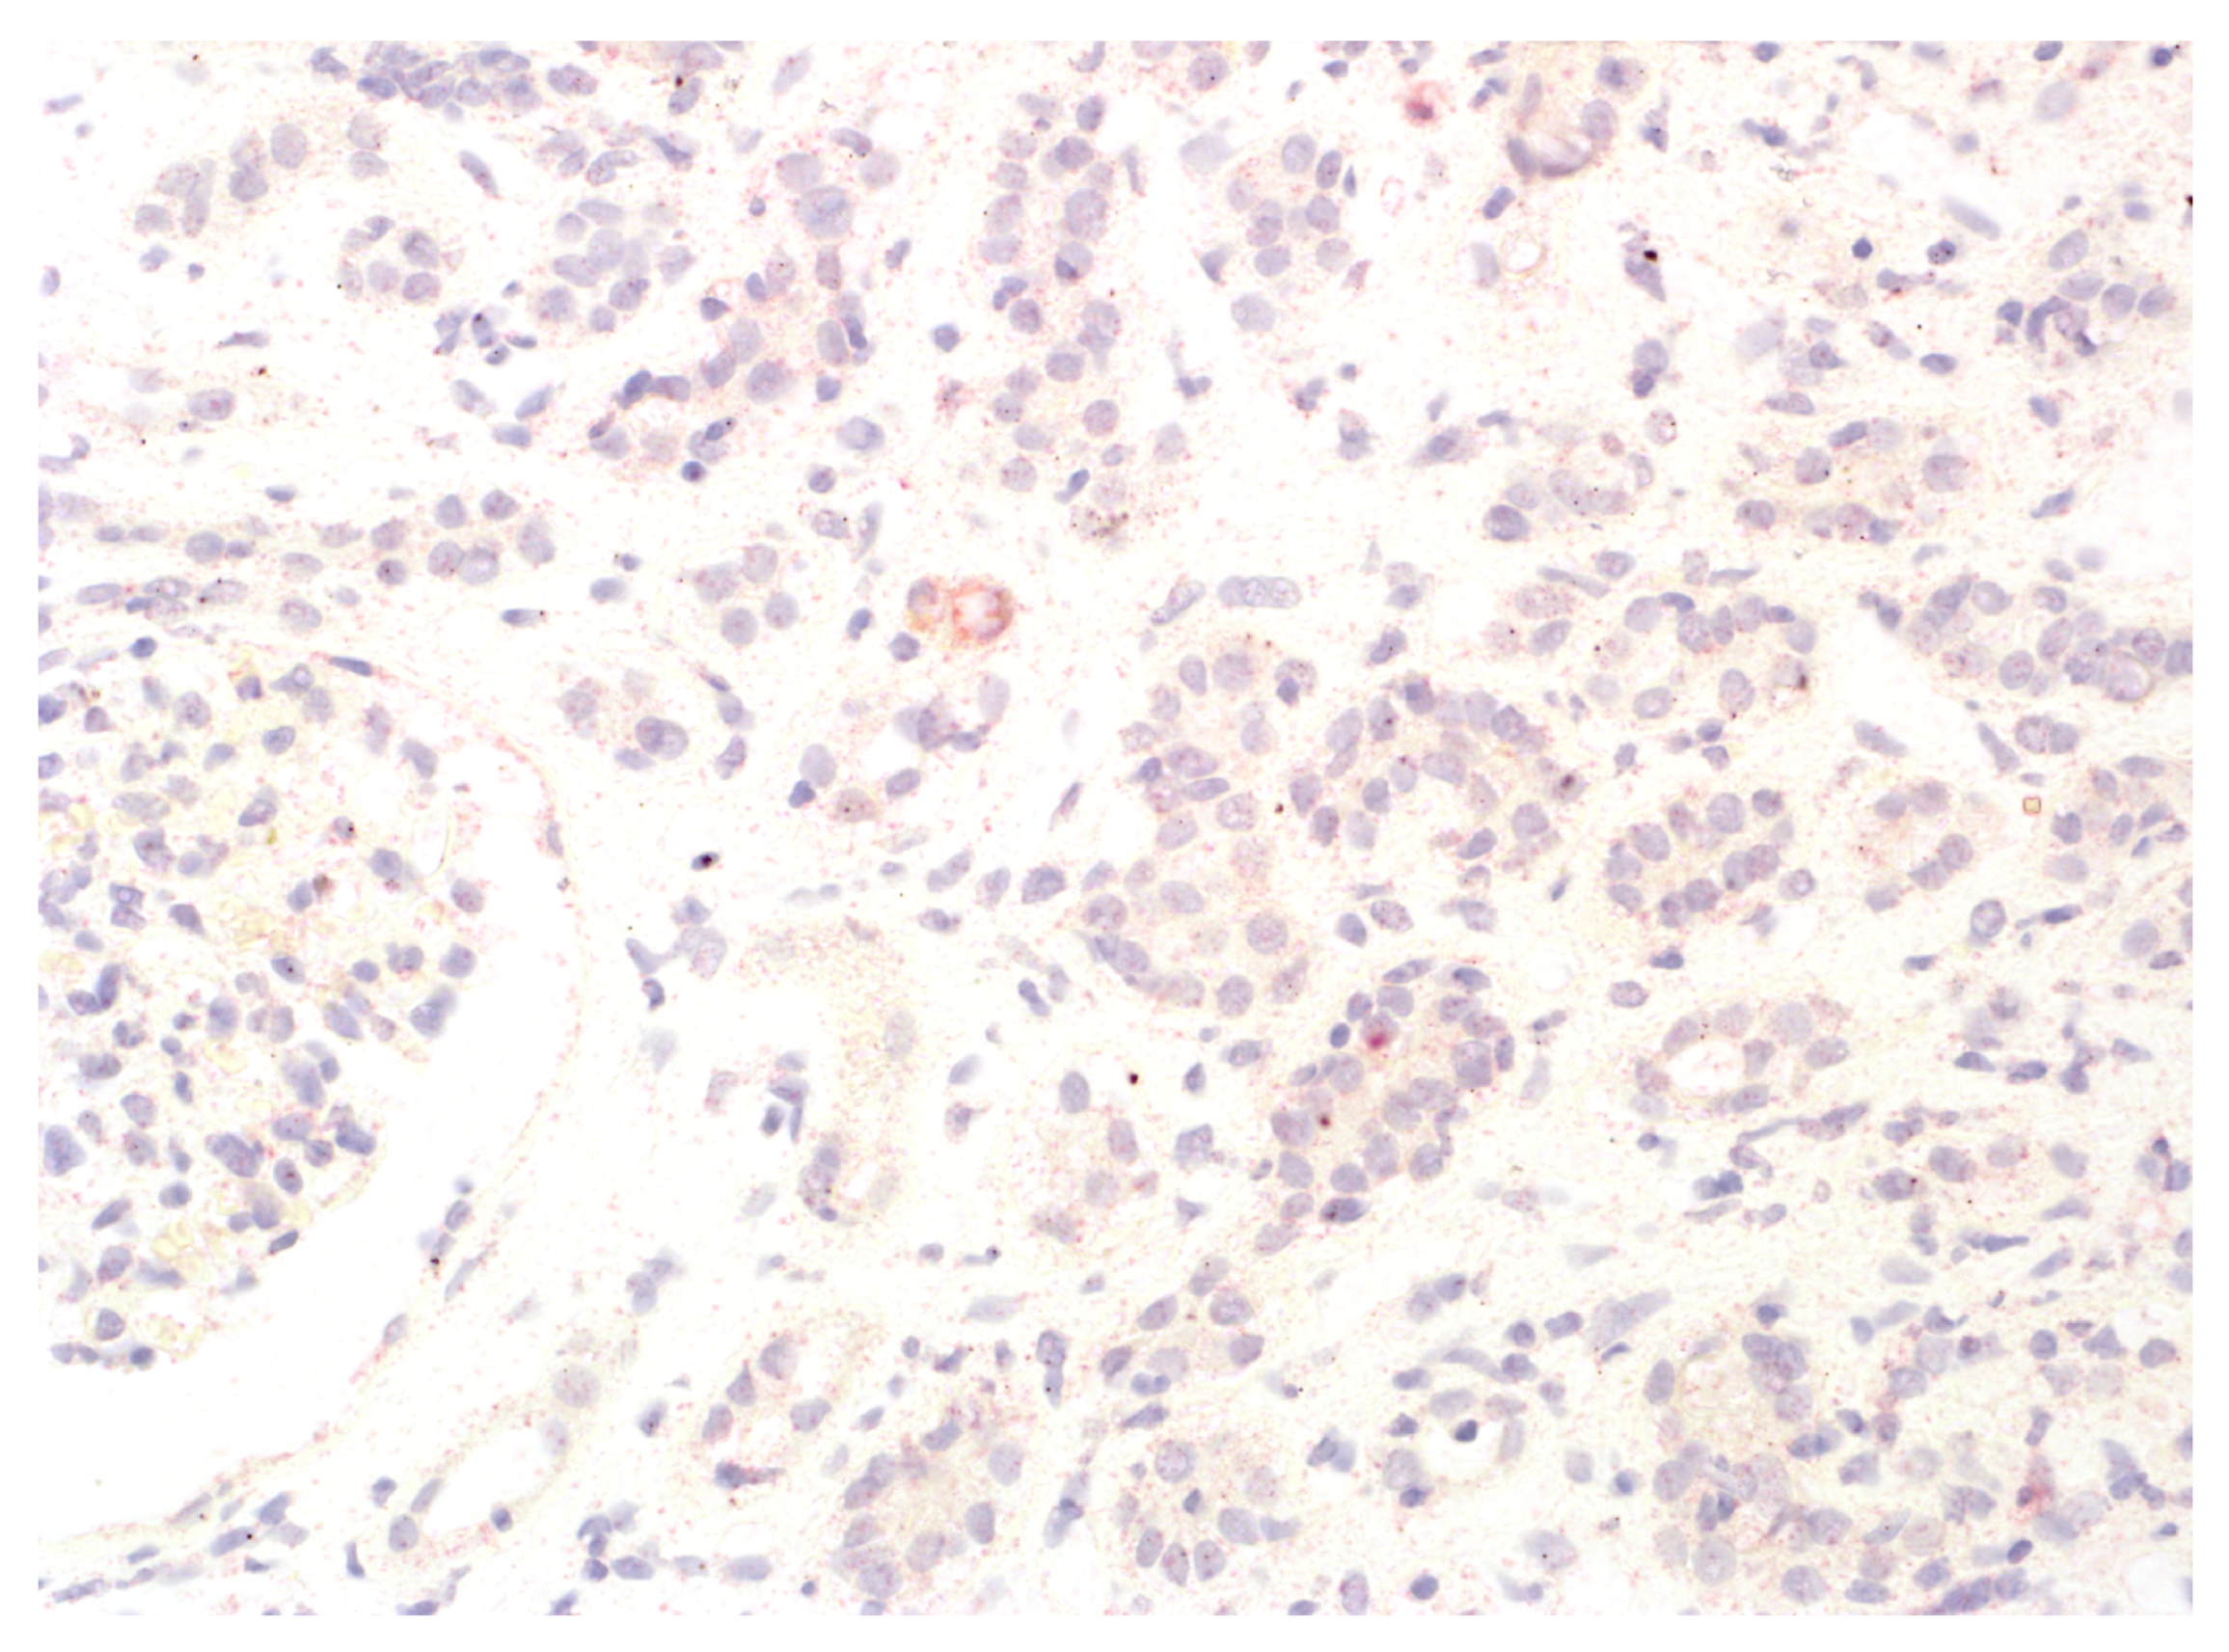

2.2. IDO1 Expression Analysis

3.2. Rejection Observed in Patients Displaying IDO1 Expression in Interstitial Foci

3.3. Analysis of Antibody-Mediated Rejection (AMR)

3.4. T-Cell-Mediated Rejection (TCMR) Analysis

3.5. Pure Types of Rejection